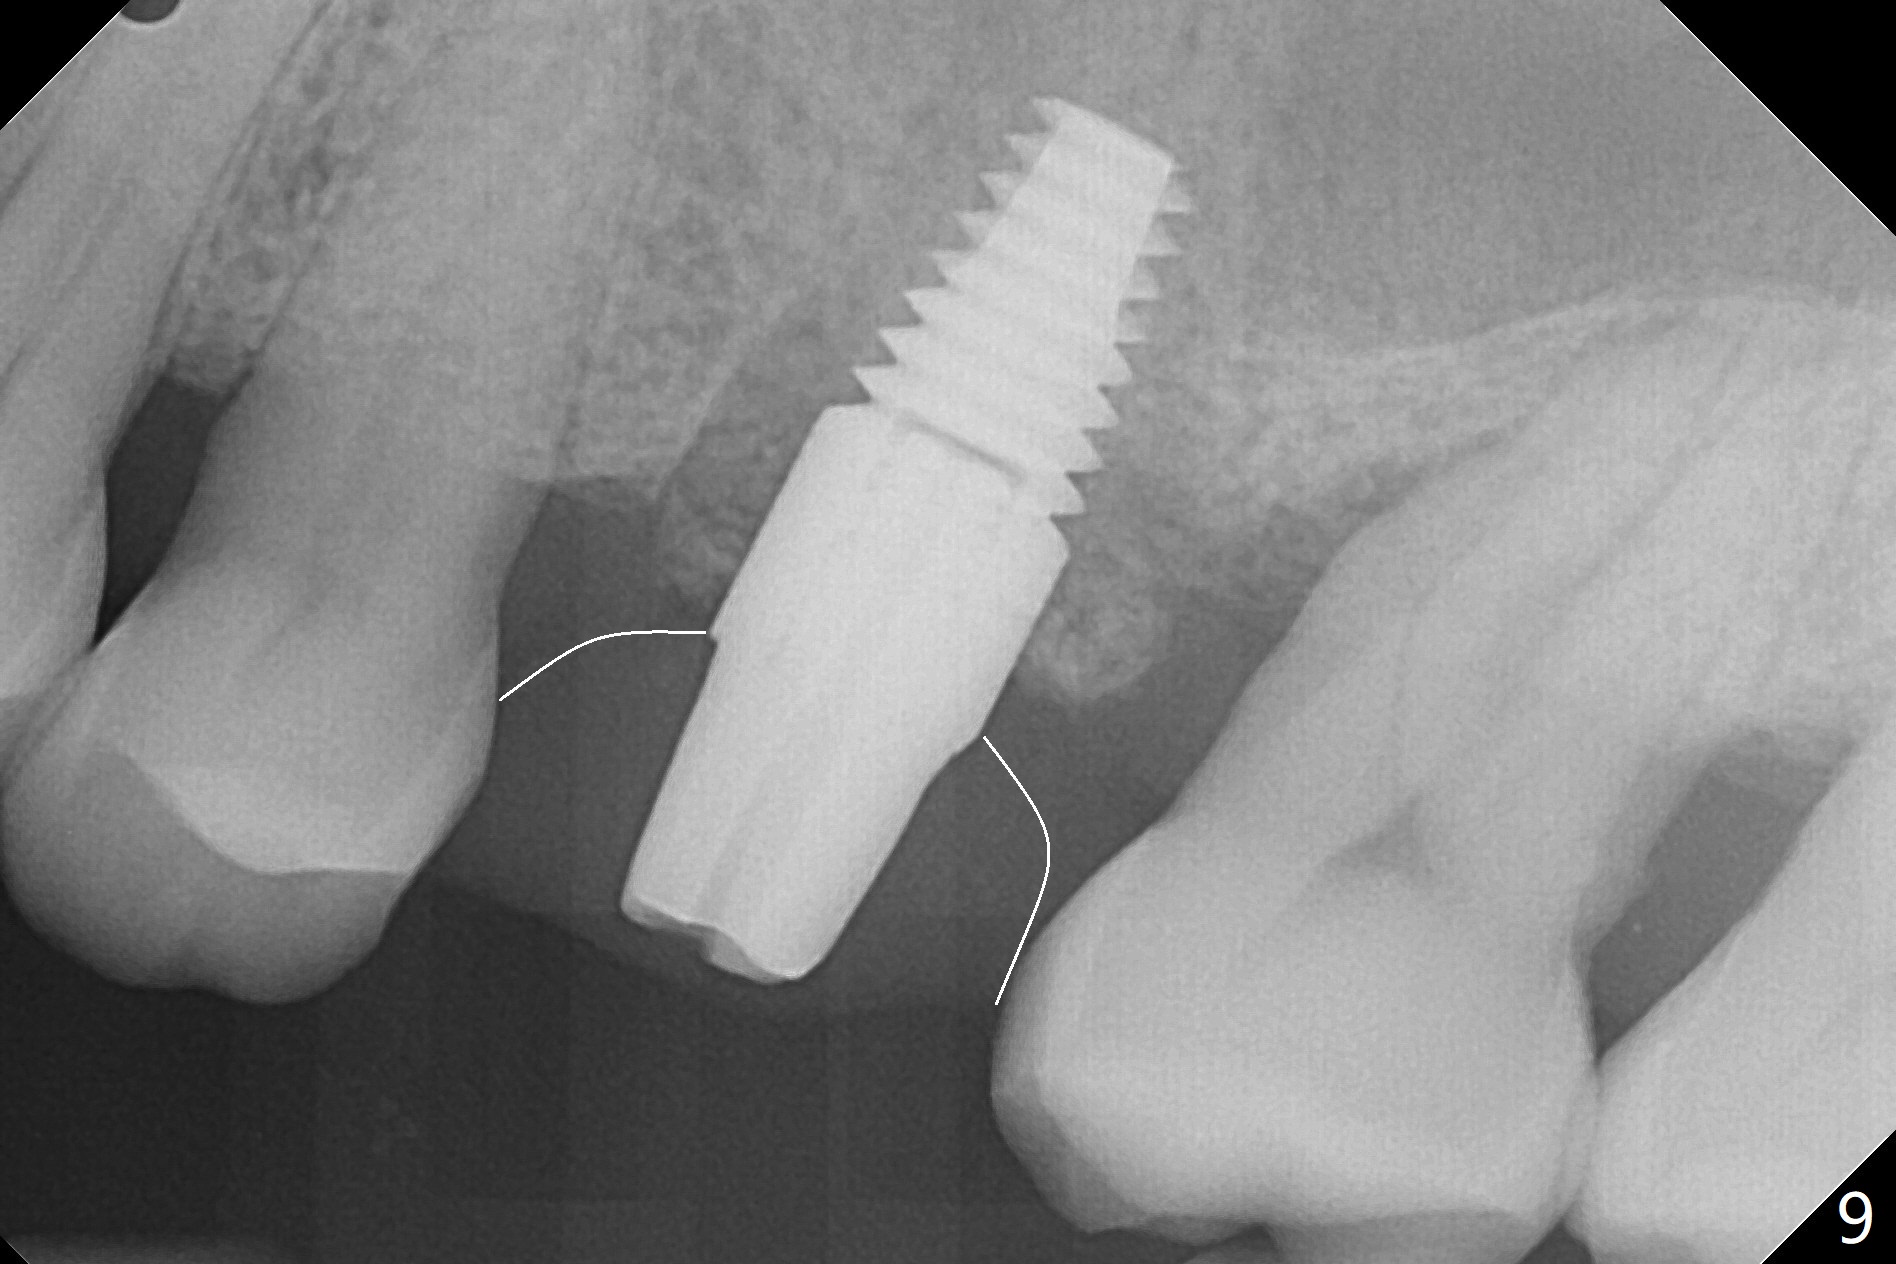

A 65-year-old man had crack tooth syndrome at #14 one month earlier (Fig.1). He shows up with crack and pain in an emergency manner (Fig.2 arrowheads). Preop CT confirms 4.5 mm bone height (Fig.3). Osteotomy will be initiated in the middle of the septum between 3 sockets (Fig.4). Depth of osteotomy is controlled with drill stoppers. After sequential osteotomy free hand, a 5x11 mm tap is used to break through the sinus floor (Fig.5) and sinus lift with Vanilla allograft. To prevent abutment screw loosening, a 5x11 mm tissue-level implant is placed; the distal thread is equicrestal (Fig.6 arrowhead). Following deeper placement of the implant (Fig.7 arrow) with a larger and longer abutment (as compared to that in Fig.6), the margin for an immediate provisional (Fig.9 white curved lines) is prepared in the coronal end of the implant (Fig.8 between arrowheads). With the tissue-level implant, the crown/implant ratio improves. Stress will be partially acting on the implant so that there is less likelihood of abutment screw loosening. The socket heals 1 month postop (Fig.10). The rough surface of the implant is exposed ~ 1 mm. With the margin modified and polished, the provisional returns to place with oral hygiene instruction. It is hoped that the gingiva will cover the exposed rough surface. The buccal rough surface remains exposed 5 months postop (Fig.11). The bone in sinus lift is mature 5 months postop (Fig.12,13). The first 1-2 implant threads are expected to be filled with mature bone in the near future (*). Since the abutment seems long enough for retention, temp bond is used for cementation (Fig.14). Water pik is being applied.